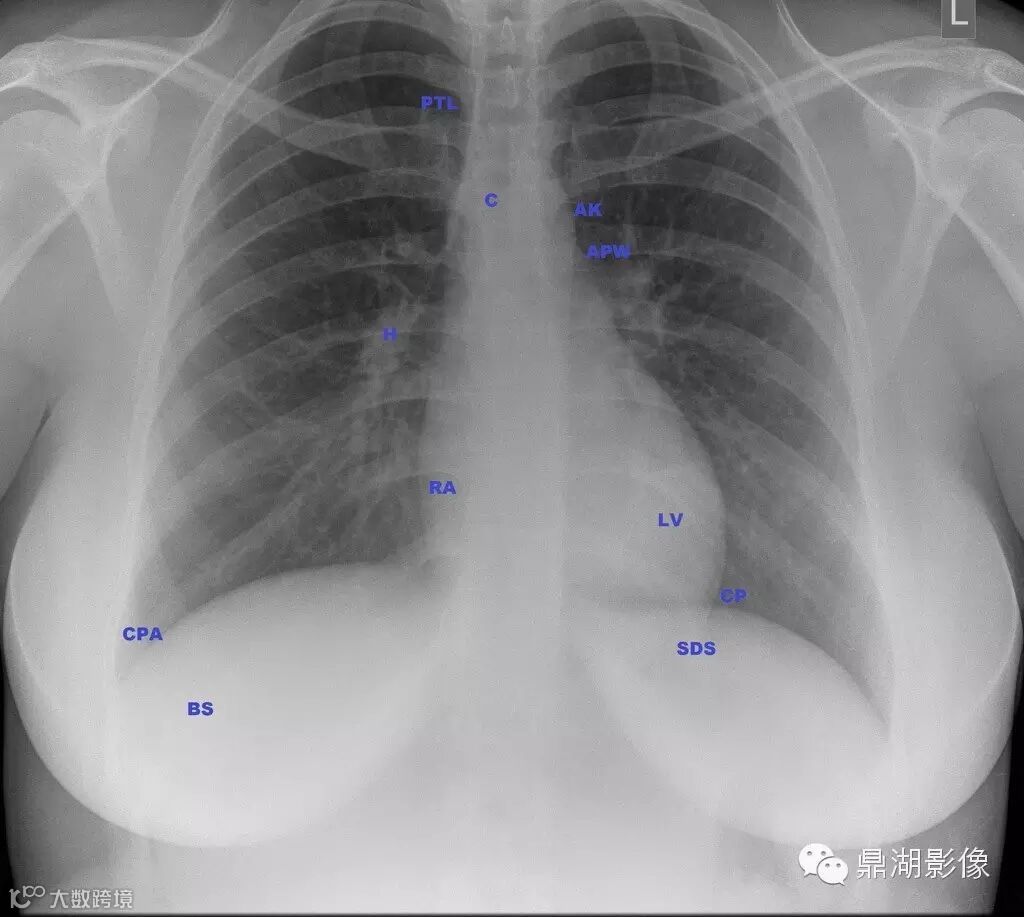

女,23岁

CPA = COSTOPHRENIC ANGLE

BS = BREAST SHADOW

SDS = SUB DIAPHRAGMATIC SPACE

CP = CARDIOPHRENIC ANGLE

LV = LEFT VENTRICLE

RA = RIGHT ATRIUM

H = HILUM

C = CARINA

AK = AORTIC KNUCKLE

APW = AORTOPULMONARY WINDOW

PTL = PARATRACHEAL LINE